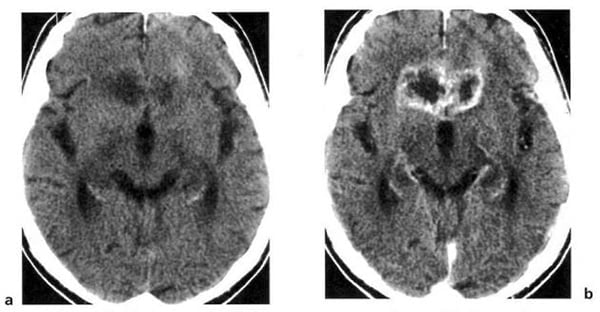

Hình 1.47. Khối máu tụ bán cấp dưới màng cứng có mật độ ngang. Trước tiêm, chỉ thấy hiệu ứng choán chỗ và xóa mất não thất bên bên trái (a). Sau tiêm (b), các tĩnh mạch bề mặt hiện lên (mũi tên) cho thấy rõ hơn ranh giới của khối tụ máu.